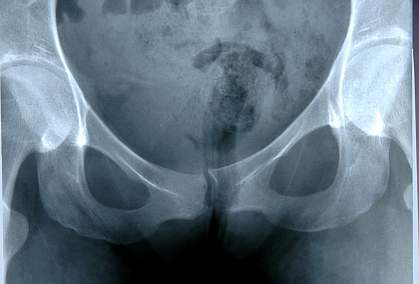

Muscles and ligaments form a sling across the opening of a woman's pelvis, holding the bladder, uterus, bowel and rectum in place. Pelvic floor disorders arise when these tissues weaken or are injured. The 3 main pelvic floor disorders are urinary incontinence, fecal incontinence and pelvic organ prolapse. In pelvic organ prolapse, organs such as the uterus, bladder and bowel collapse onto the vagina and cause a bulge through the vaginal canal. Pelvic organ prolapse can be uncomfortable. All 3 disorders can make physical activity difficult and interfere with sexual functioning.